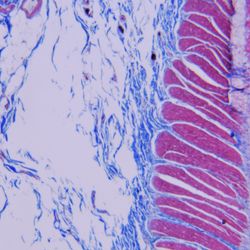

The testing reality is starkly different in immunohistochemistry (IHC), a test format widely used in surgical pathology to evaluate cancers in tissue samples and determine correct treatment. IHC lacks reference standards, assay calibration is nonexistent and, until now, the technology for incorporating traceable units of measure to standardize IHC assays was unattainable.

IHC is almost always a qualitative test format; the test result is positive or negative. Just by guessing, you would have a 50/50 chance of delivering the correct test result. The overwhelming consensus of published data show that by performing IHC testing and not guessing, we only increase the rate of accurate test results from 50 percent to 70–90 percent. In other words, the error rates in IHC are at least 10 times those of blood testing laboratories.

The implications of IHC test variability are huge for cancer patients, prescribing physicians, pathologists, and clinical lab managers. Lab-to-lab variation leads to false positive or false negative results, meaning patients are potentially misdiagnosed and/or receive the wrong treatment, or need to be retested.